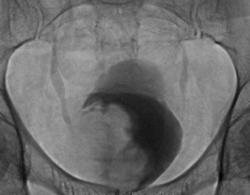

Фрагменты рентгенограмм с увеличение изображения мочевого пузыря.

Да. опухоль мочевого пузыря весьма больших размеров и занимает по всей видимости не менее 3/ объёма мочевого пузыря.